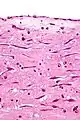

| Micrograph of an atrial myxoma. H&E stain. | |

Atrial myxoma and myocardium. H&E stain.

Atrial myxoma. H&E stain.

Atrial myxoma covered by endothelium. H&E stain.